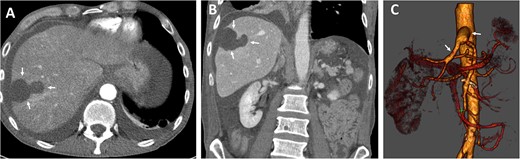

Various antibiotics were started, including meropenem 1 g every 8 hours, vancomycin 1 g every 12 hours, and cefuroxime 500 mg every 8 hours. Computed tomography performed showed occlusion of the celiac trunk and the superior mesenteric artery with prominent collateralization through the inferior mesenteric artery (Fig. 2). The intrahepatic portal vein was patent. In addition, hypodense lesions were found in the liver, which most closely corresponded to hepatic ischemia. The indication for surgical reconstruction was made. We performed an antegrade visceral reconstruction with a bifurcated 12-6 mm Dacron graft from the supra-celiac aortic donor to the superior mesenteric and celiac arteries without any complications.

Preoperative axial (A) and coronal (B) CT angiographic images demonstrate hypoenhancement of all of the hepatic parenchyma and hypodense, hepatic lesion measuring 48 × 47 × 34 mm in the segment V and VI (arrows). (C) 3D reconstructed CT angiography shows occlusion of the celiac and superior mesenteric arteries (thick arrows) and hypertrophy of the inferior mesenteric artery and artery of Drummond (thin arrow).